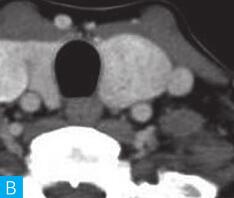

甲状腺CT检查:CT检查设备为256层iCT,病人采取仰卧位,扫描范围自外耳道平面至下颌角以下,常规扫描层厚为0.9mm、层间隔0.9mm,电压120kV,管电流280mA,矩阵512×512;经右肘静脉团注法增强扫描,碘海醇80ml,流速4ml/s,动脉期25秒扫描,静脉期60秒扫描。见图1。

图1 甲状腺CT

A、B.甲状腺CT横断面平扫;C~H.甲状腺CT横断面增强

CT平扫可见甲状腺左叶圆形以低密度为主病灶,大小为8.0cm×6.5cm,边界清晰,边缘尚光整,其内密度不均匀,低密度区CT值18HU,部分密度稍高,并可见斑点状粗大钙化影;CT增强后,甲状腺左叶病变呈不均匀渐进性强化,结节状改变,动脉期强化区CT值99HU,静脉期CT值85HU,且强化范围增大,提示该病变的血供较为丰富,应该考虑肿瘤样病变,结节性甲状腺肿可能性大。

本病例CT扫描发现起源于甲状腺较为容易,但要观察病变是囊性、实质性或囊实性及其供血,CT增强扫描十分必要,易于显示囊实性病变及其供血情况,其结节状改变更加显著,有助于判定病灶的血液供应情况。本病例基本征象为类圆形、边缘清晰、内粗大钙化、结节状强化之肿块。